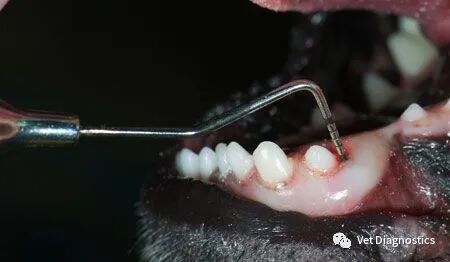

获得长期积极结果的更健康的牙科方法是首先检查有意识的患者(包括口腔),然后在全身麻醉下进行逐牙检查(包括探查和口腔内x光片)。如果牙齿和支撑结构状态良好,继续下一颗牙齿。如果没有,诊断病理并制定治疗和预防计划(图1A-1D)。

图1A.沿左上颌第四前磨牙近中面的12mm探测深度;指示拔牙。(所有图片由Dr. Jan Bellows。)